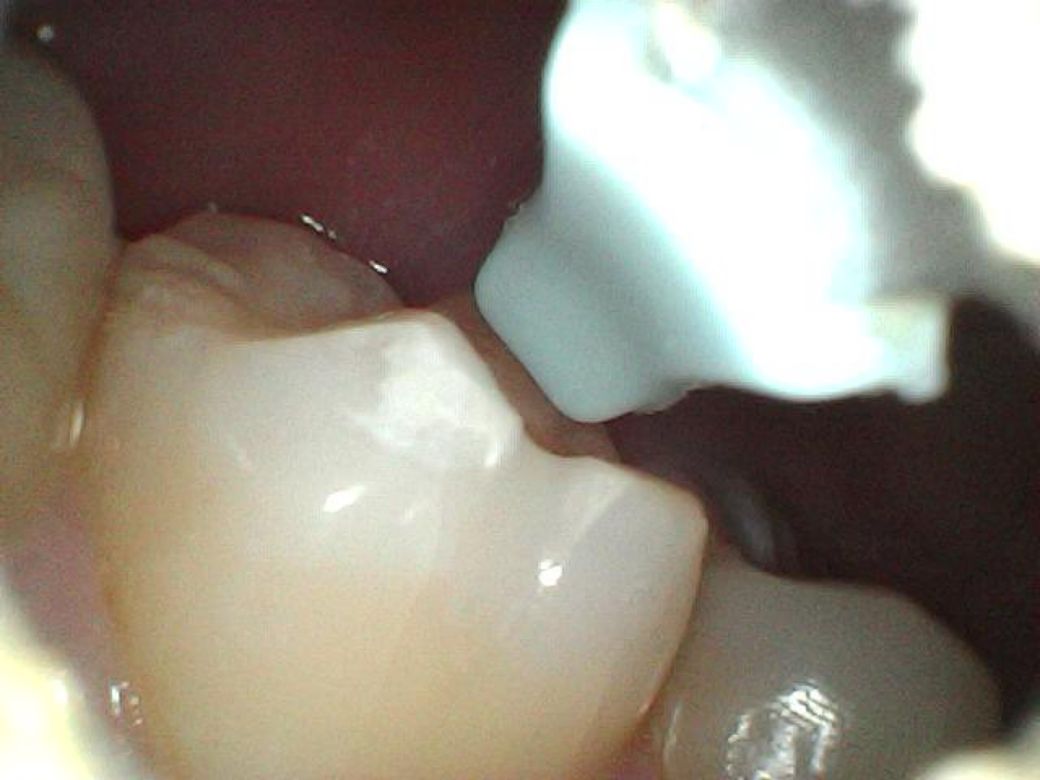

이빨에 뭔가 하얀 것이 생겼어요, 충치인가요?

제가 이

닦고 혀로 스캔하는 버릇이 있는데 그 전까지는 느껴지지 않다가 어제부터 왼쪽 어금니 옆에 만져지는 무언가가 생겼어요.

제가 내시경 귀이개가 있어서 들여다봤는데 치석인지 충치인지 모르겠네요..

혀로 만지는 촉감은 현무암같이 꺼끌꺼끌한 돌덩이 같기도 하고.. 뭔가 부식된 것 같은 촉감도 느껴져요

어제 아침, 오늘 아침 이틀동안 찍은 사진들인데 이거 혹시 사진으로 뭔지 구분이 가능할까요?

어제보다 크기가 좀 줄어든 느낌이라 치석인가

싶어 다행은 한데..

처음 두장이 어제, 나머지가 오늘 사진입니다

어제

특별히 무엇이 보이지는 않습니다. 크기가 줄어든 것으로 보인다면 충치보다는 치석일것 같습니다.

사진만으로 정확히 파악은 어려우나, 현재 초기 충치단계로 보이기에 빠른시일내에 치과에 방문하여 상태를 확인하고 치료를 받길 권합니다.

치석의 형상은 아니고 초기충치 내지는 이전에 떼운재료가 떨어지거나 마모된 것 같습니다 치료가 시급한 정도로의 충치는 아닌것 같습니다